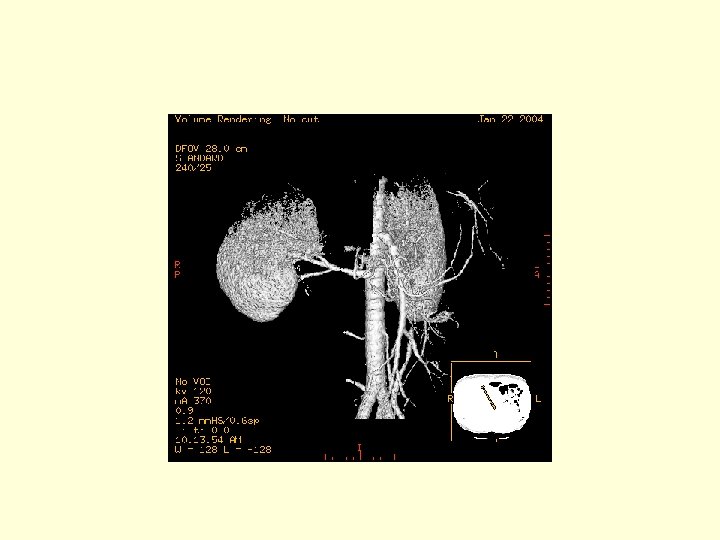

This is a 3 D image showing the branches of the SMA.